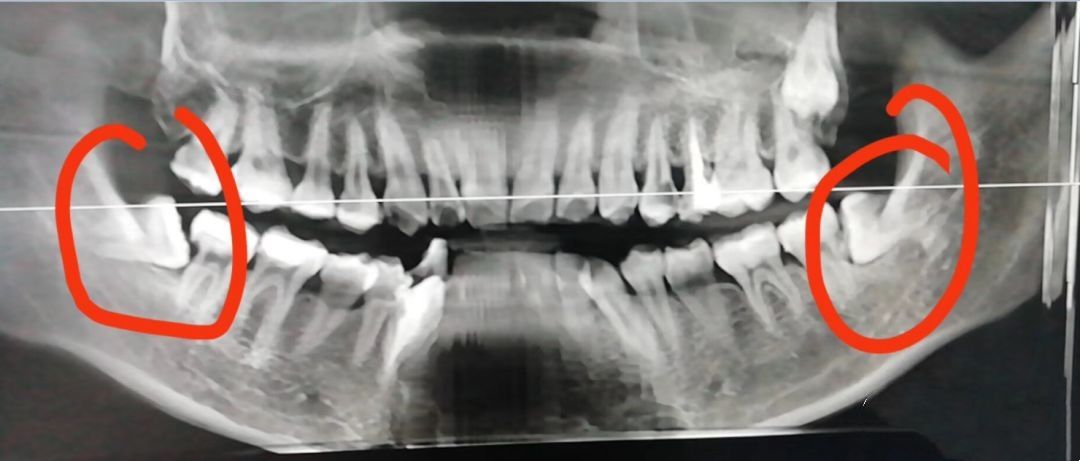

1.位置不正,常见于下颚智齿

智齿向前生长挤压到邻牙。此外,向后、向舌侧、向颊侧、甚至向下长也都可能产生危害。

智齿生长方向不正常,通常会导致智齿与相邻的磨牙间出现缝隙或凹槽,极易嵌顿食物残渣,长时间清理不净,相邻磨牙将发生龋齿、牙髓炎、根尖炎等。

3.牙齿咬合错位

人最多会长四颗智齿,有些人会长出一颗,有些人会长出几颗,当智齿蒙出来的时候很容易造成没有相应的牙齿进行咬合,从而造成咬合异常。